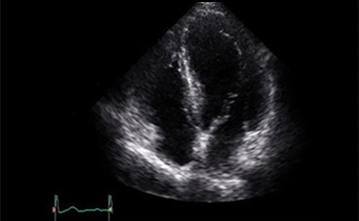

초음파를 이용하여 실시간으로 심장의 움직이는 모습을 관찰할 수 있으며 심장의 해부학적 구조의 이상, 판막질환, 심장수축능력평가, 심장내 압력, 허혈성심질환 등을 비침습적으로 관찰할 수 있는 검사법입니다. 특별한 전처치나 금식이 필요없는 검사이며 왼쪽으로 돌아누워 가슴에 탐촉자를 대고 시행하는 검사입니다. 30분에서 1시간가량 소요될 수 있습니다.